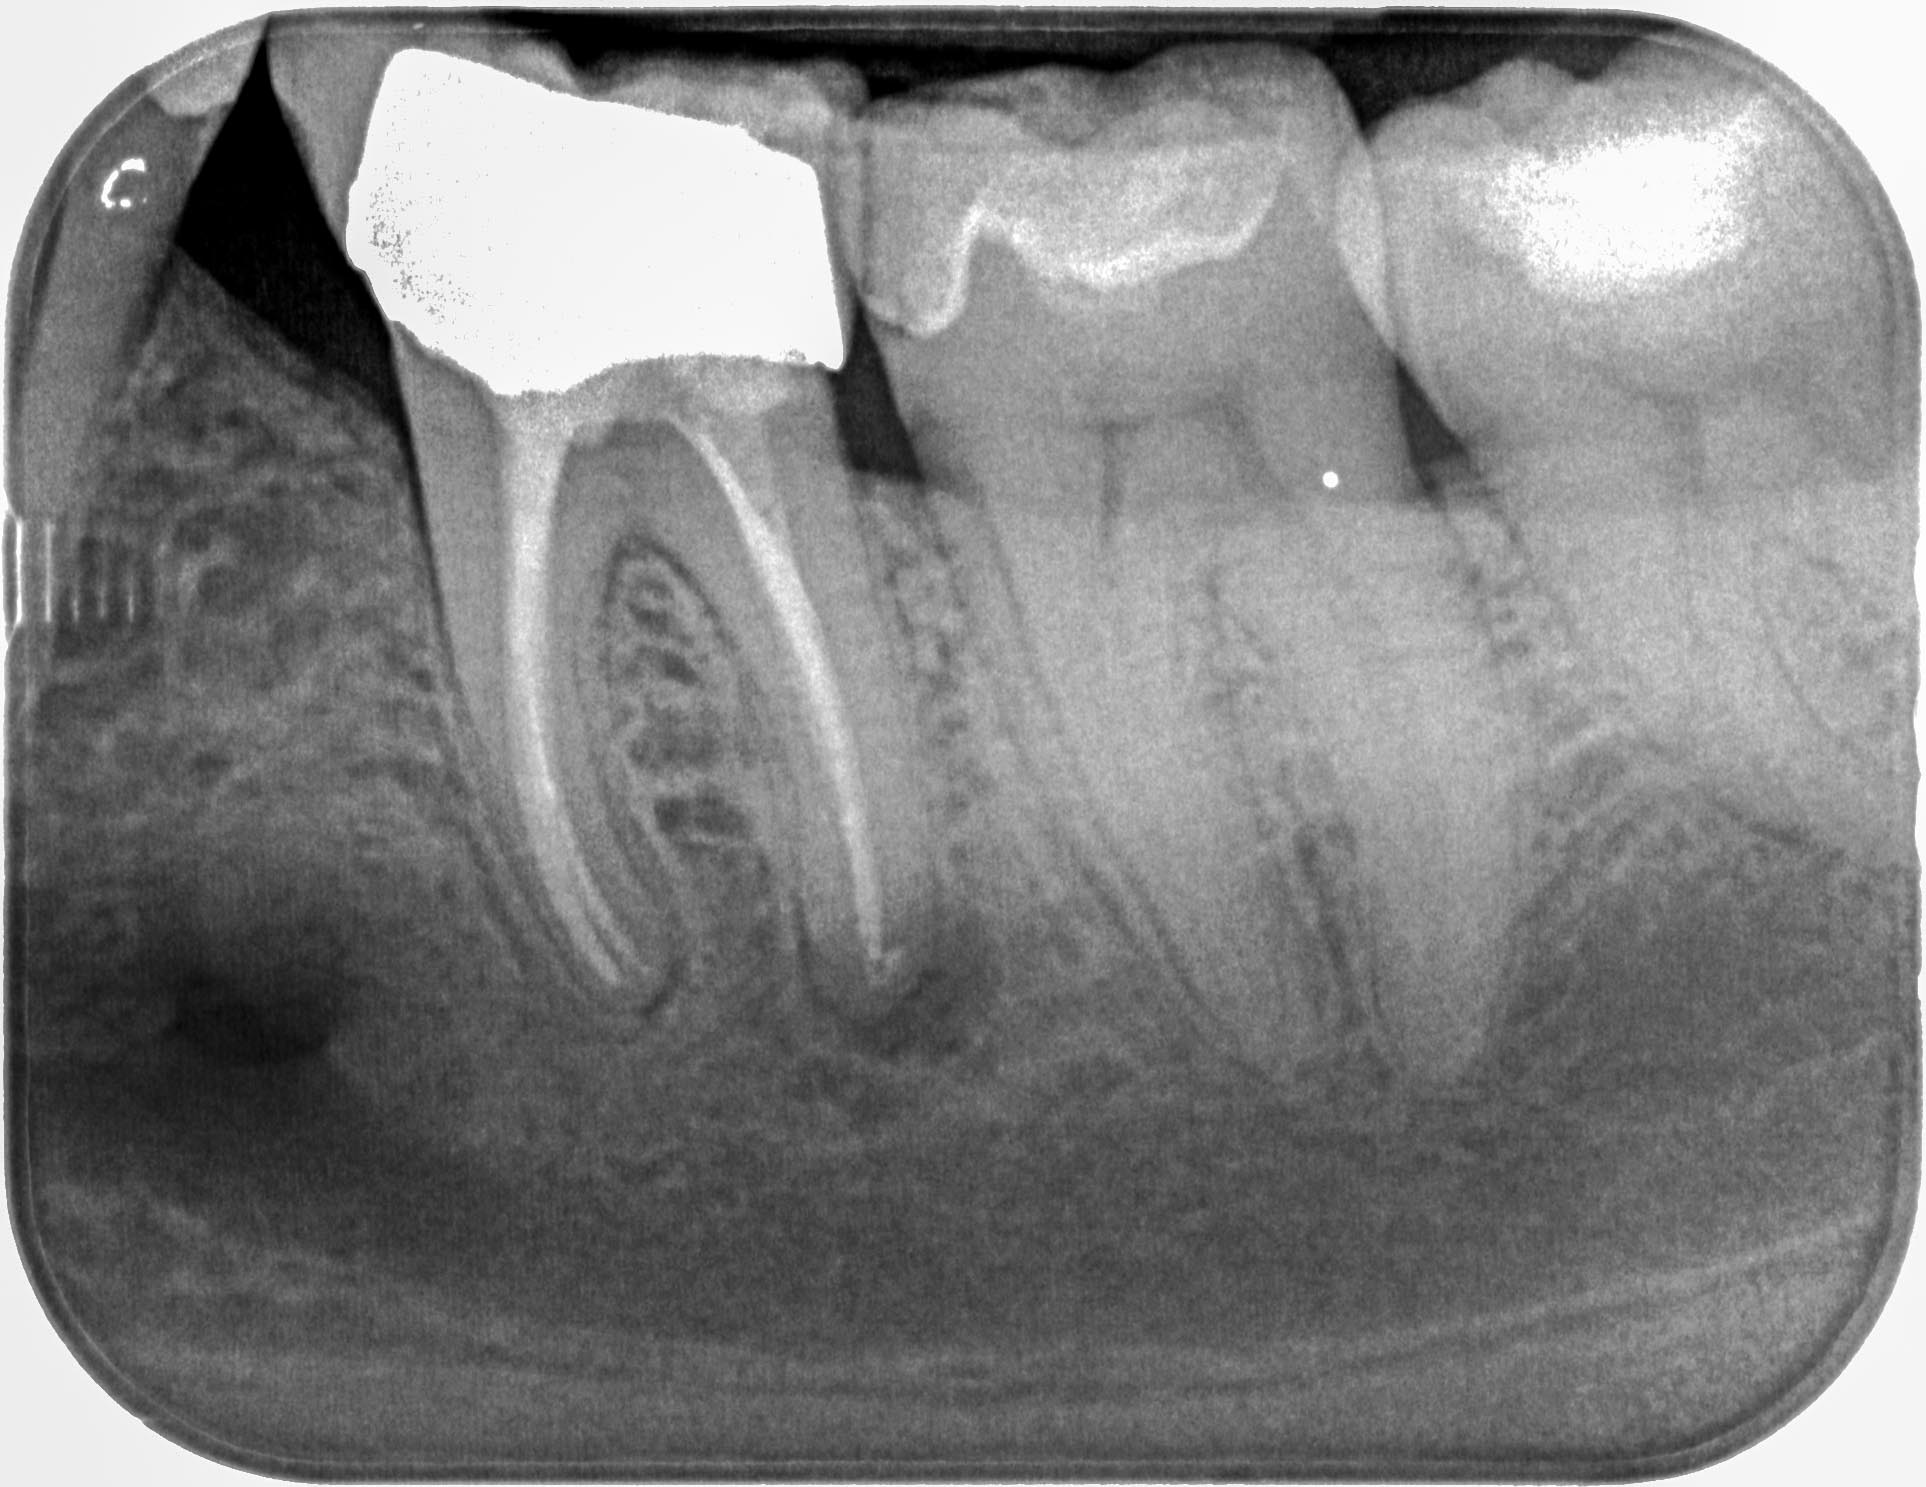

SP24 (3 von 5) Veröffentlicht 4. Juli 2016 am 1926 × 1487 in Dentikel als Ursache von Zahnschmerzen ?